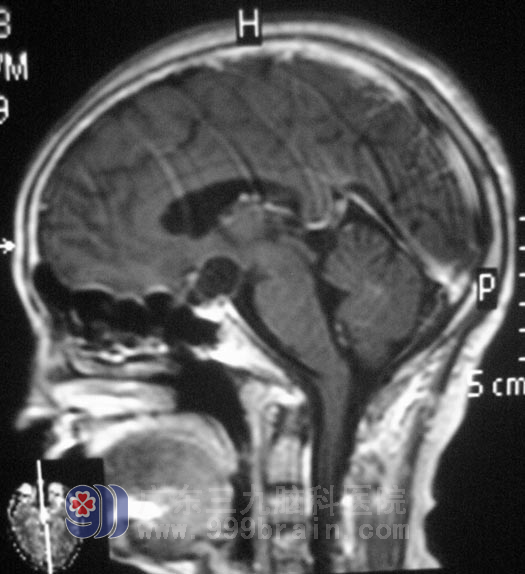

黄阿姨今年5月份左右开始出现视力下降。9月份到当地省人民医院就诊,MR检查提示鞍上区占位,大小约2.2cm×1.5cm,初步考虑为颅咽管瘤。18日在当地医院行手术治疗,头皮切开后,黄阿姨出现麻醉药物过敏性休克,紧急中止手术,进行抢救;住院二十多天后,黄阿姨恢复了正常。http://www.999brain.com/

▲术前MR